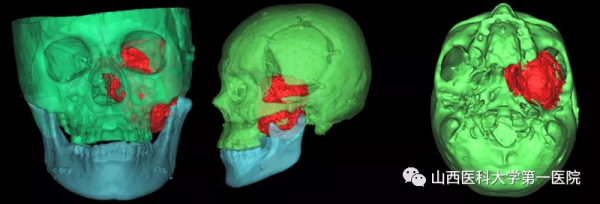

經過對“手術入路、硬腦膜修補、顱底缺損重建、頸內動脈和海綿竇等毗鄰結構保護”等系列高風險環節的反覆研究,最終定為由口腔頜面外科先行頸-頜入路、上頜骨、顴骨部分切除,充分顯露後先切除顱外3/4部分瘤體,再透過顱底骨缺損“視窗”由神經外科完成顱內部分瘤體的切除與硬腦膜的修補,最後採用股前外側肌皮瓣遊離移植修復顱底、翼顎窩、顳下窩巨大無效腔。為了使手術方案進一步可靠,口腔頜面外科團隊術前採用數字化技術對手術入路進行了虛擬驗證,並從三維立體方向對腫瘤周圍的重要結構進行全方位掌握。